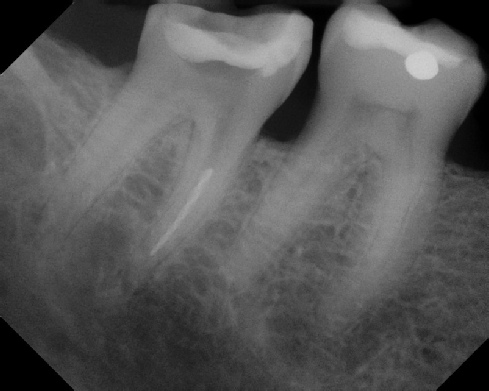

Pre-op Post-op 1 Post-op 2